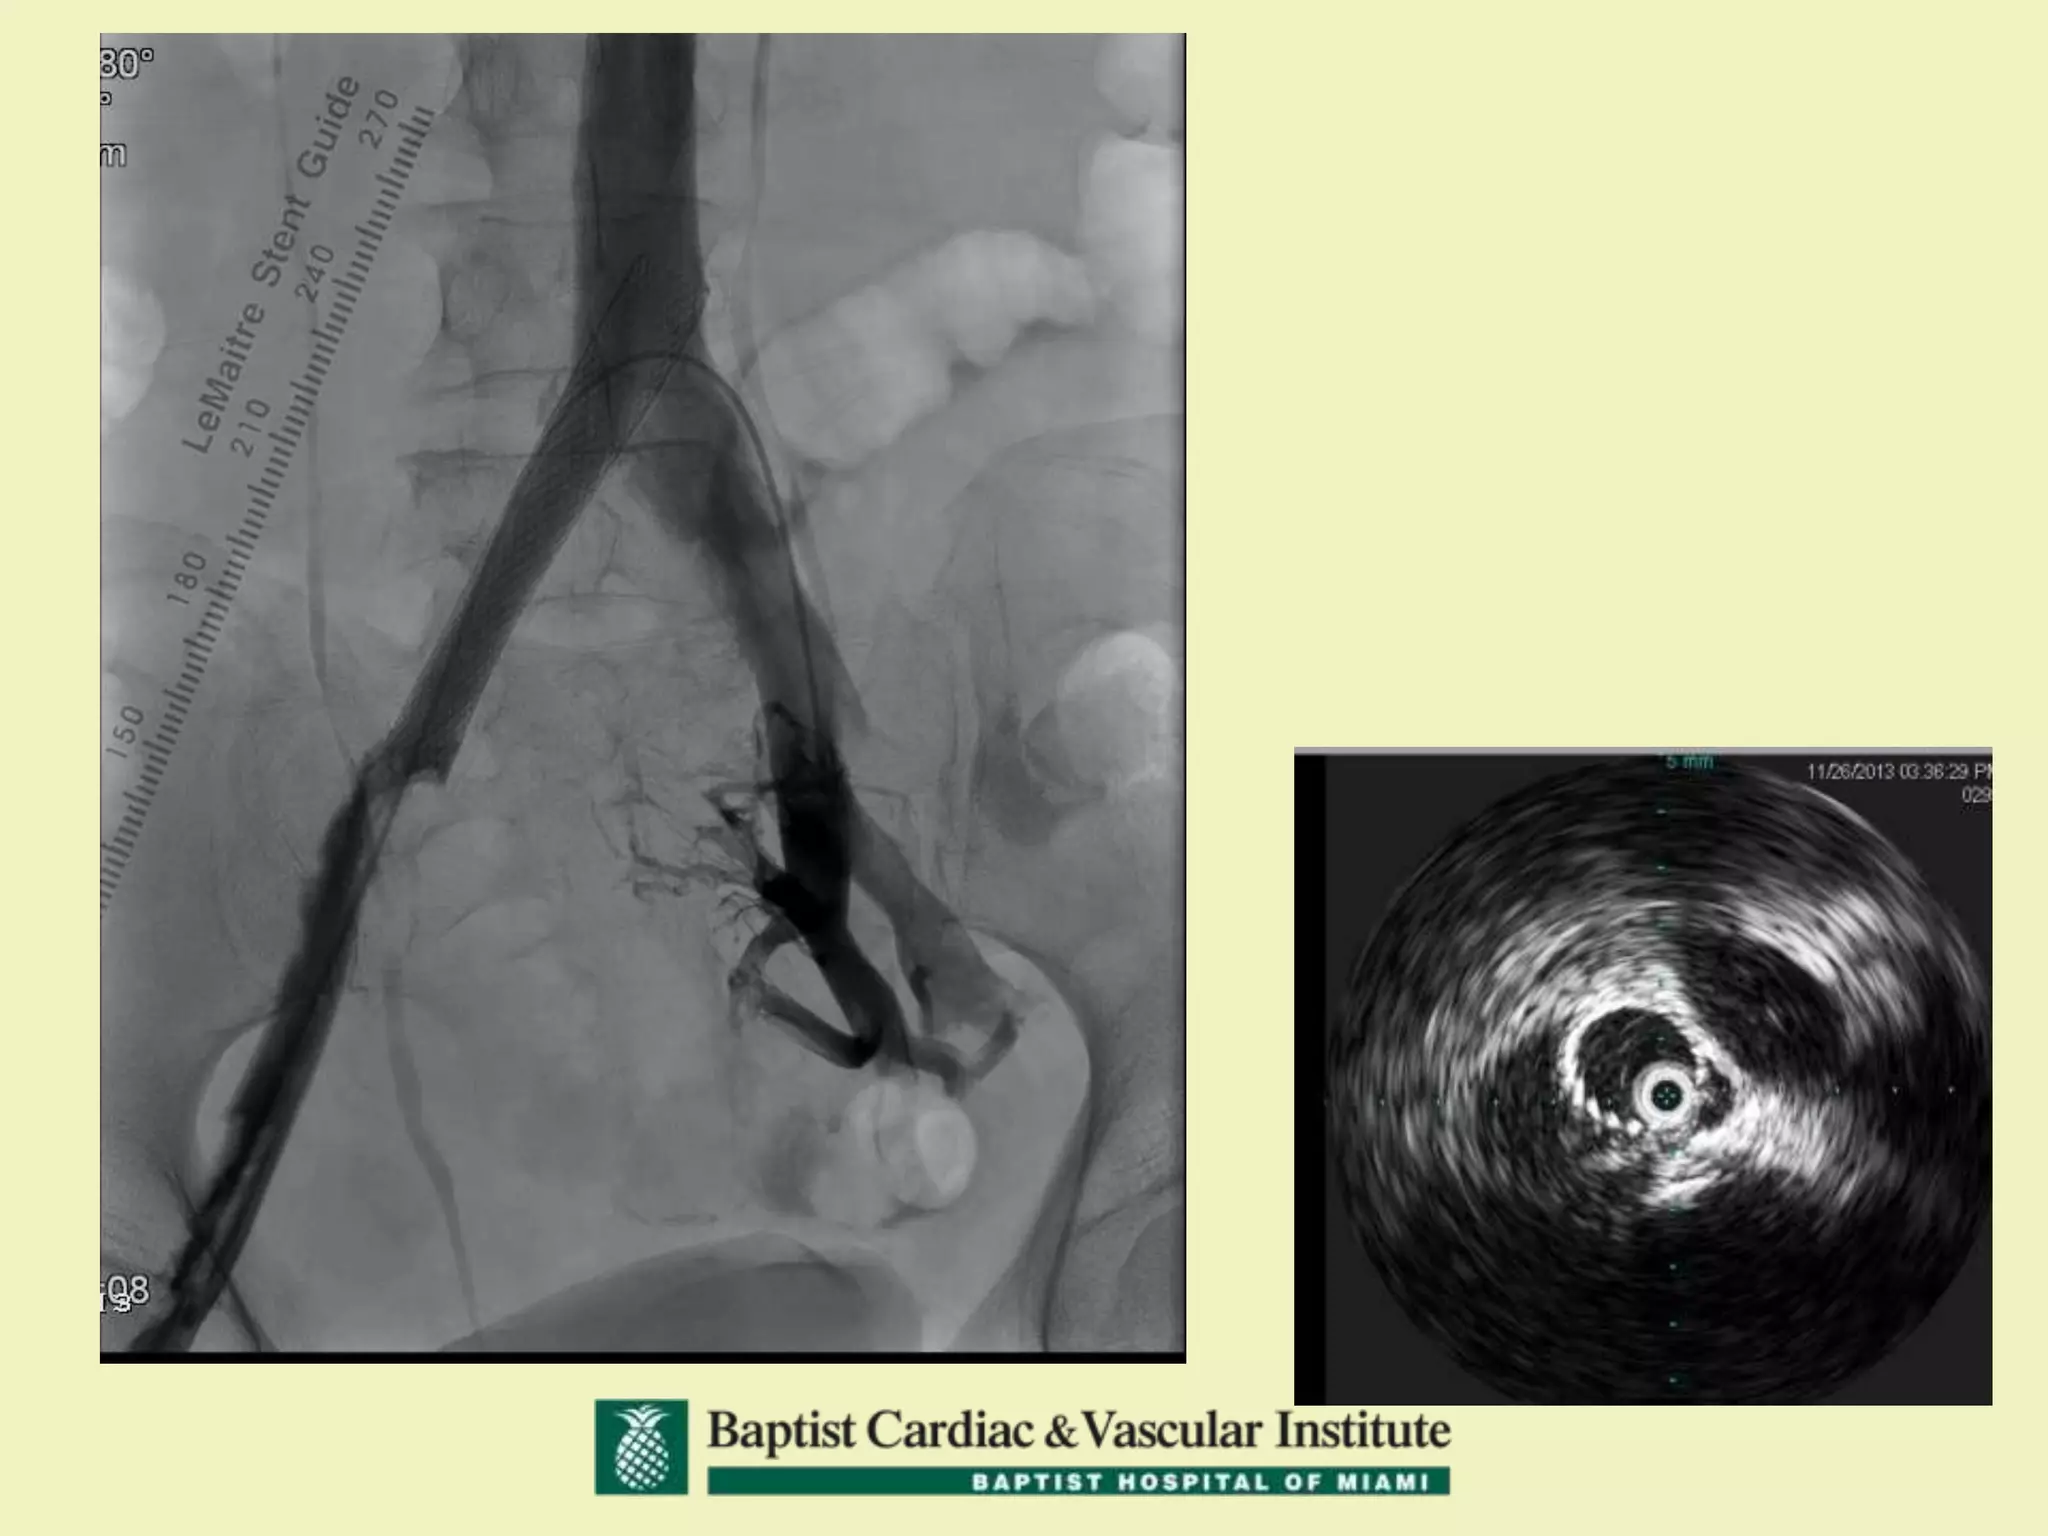

68 yo with Left Leg Swelling and

Left DVT

68 yo withLeft Leg Swelling and Left DVT